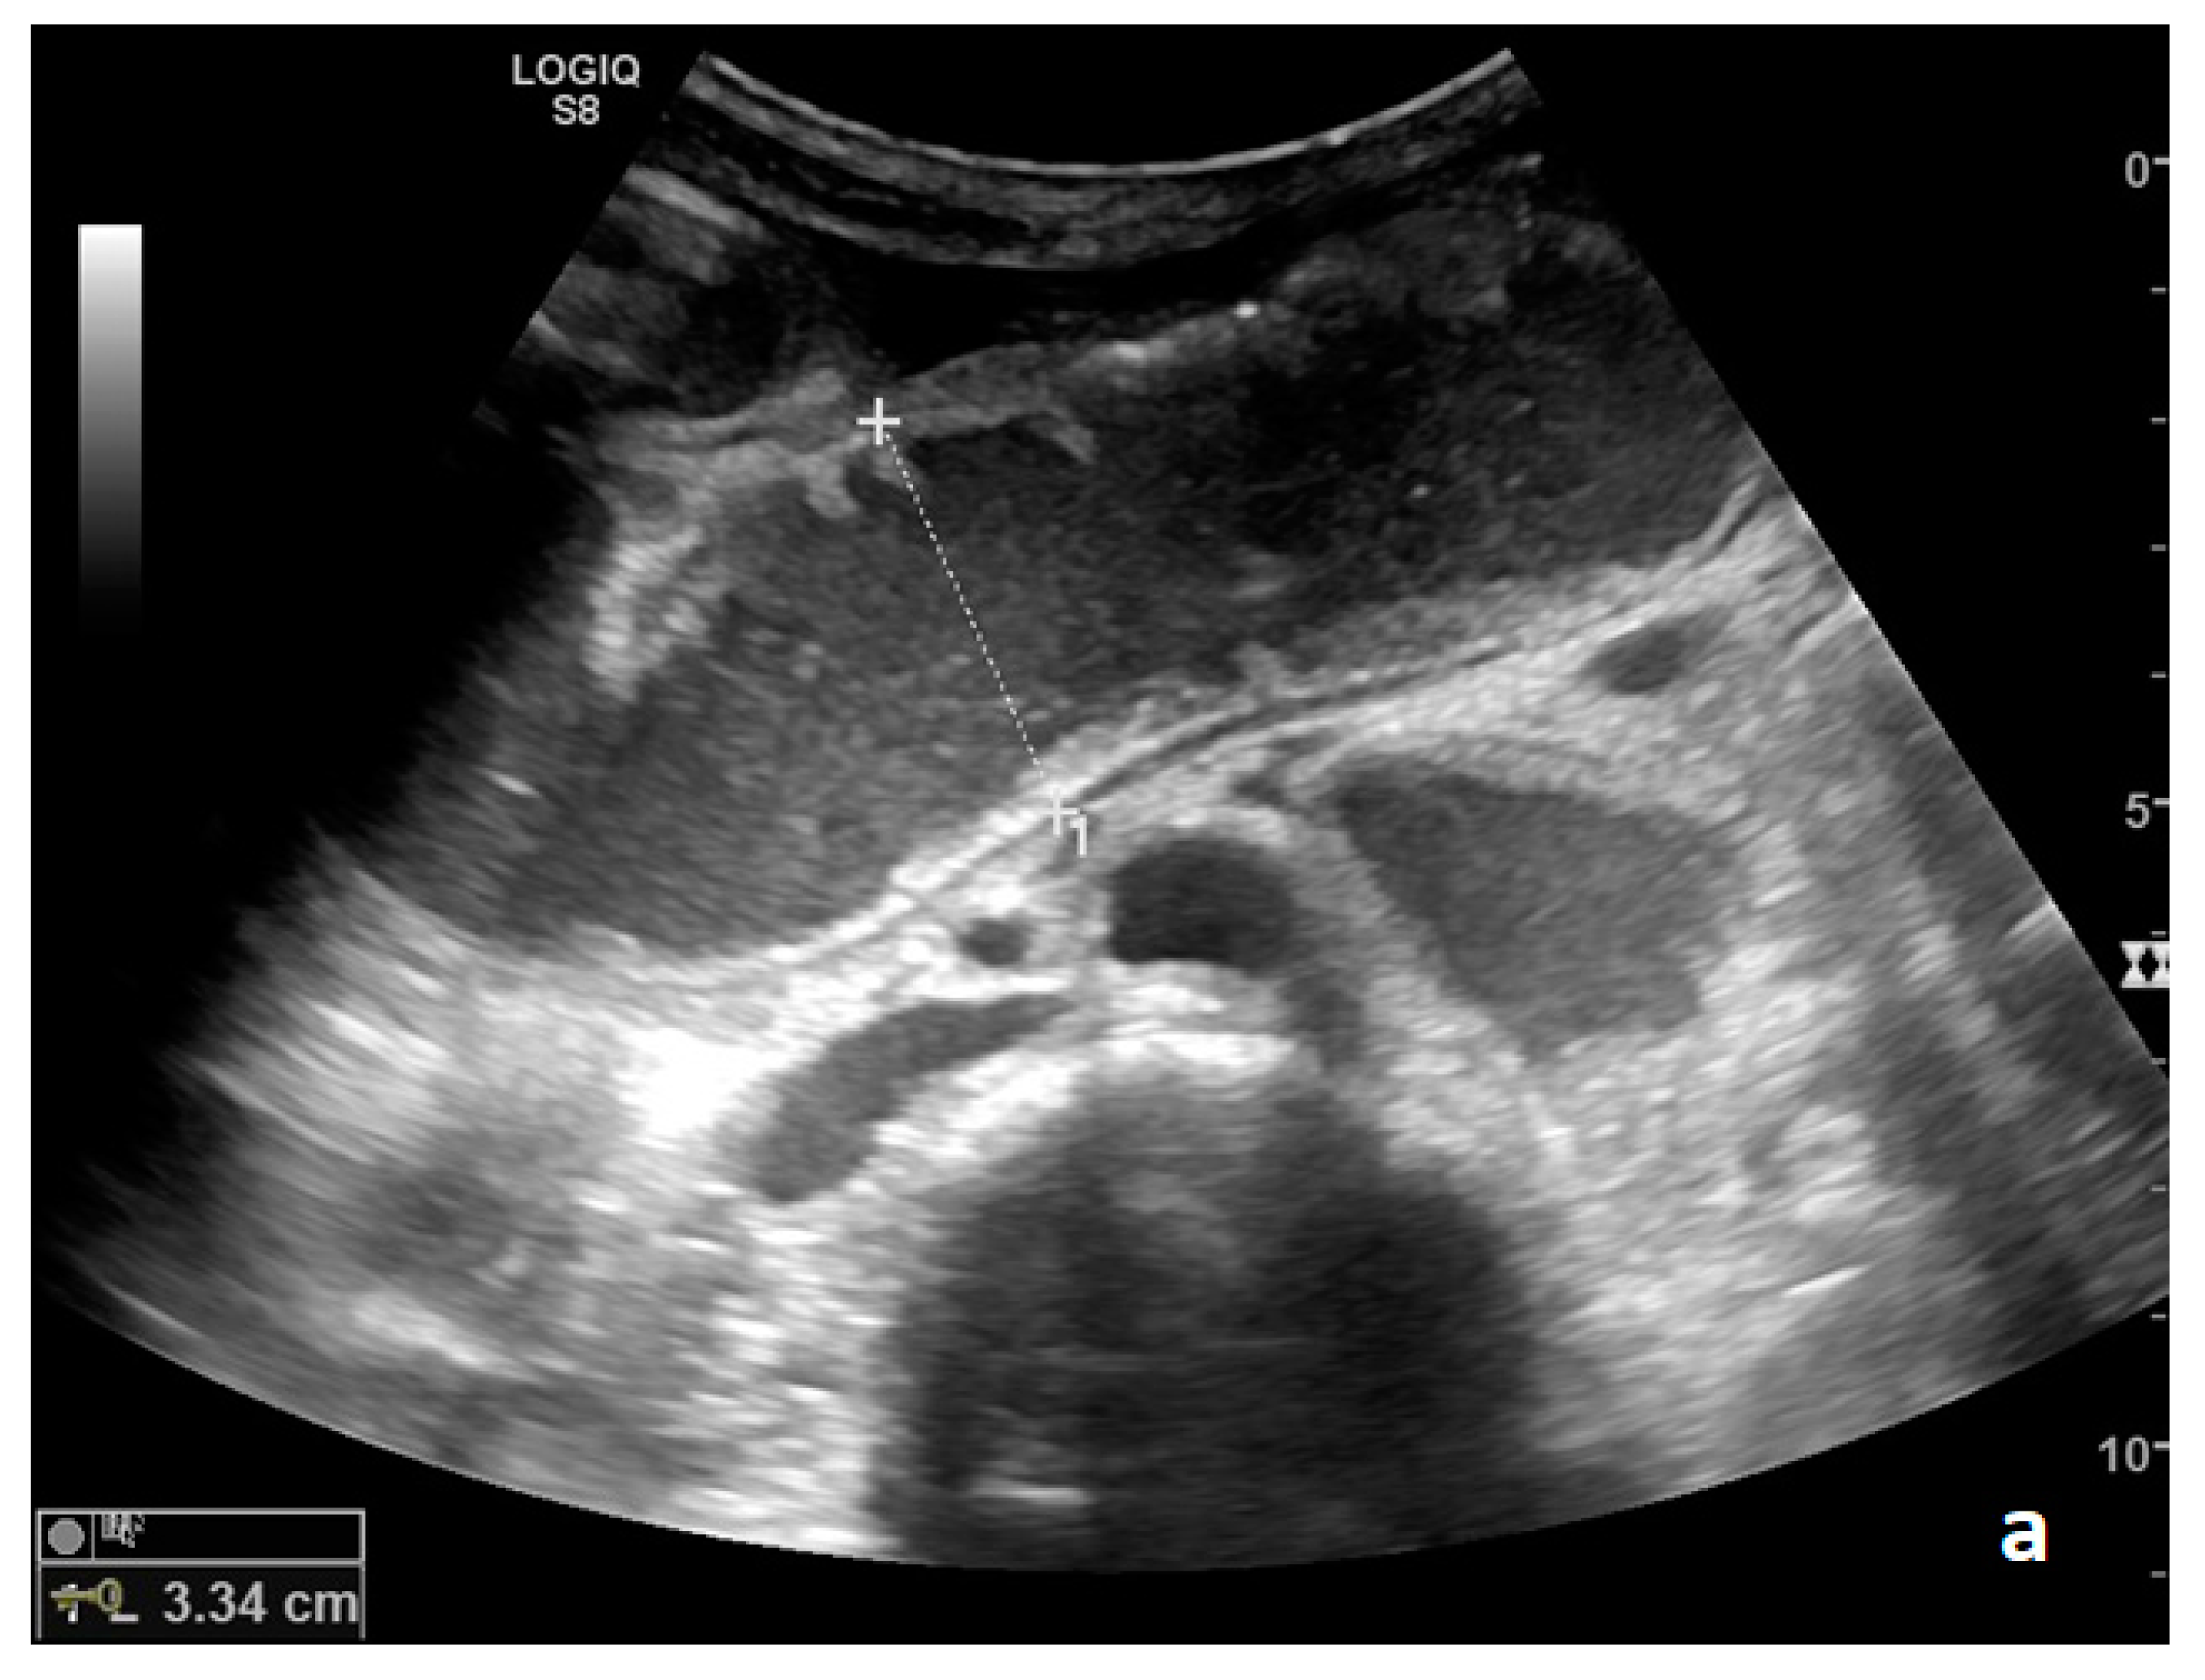

Figure 1.

(a,b). A simple SBO. Ultrasound images show fluid-filled, dilated small bowel loops (a,b) with hyper-kinesis and hyper-representation of valvulae conniventes (white arrow) (a); tail comet artifacts are visible due to air-fluid levels (dashed arrow) (b) and groups of bowel loops with severe differences in diameter (‘bowel jump diameter’) are evident more superficially (*) (b). No free fluid was detected in the abdominal cavity or between bowel loops.